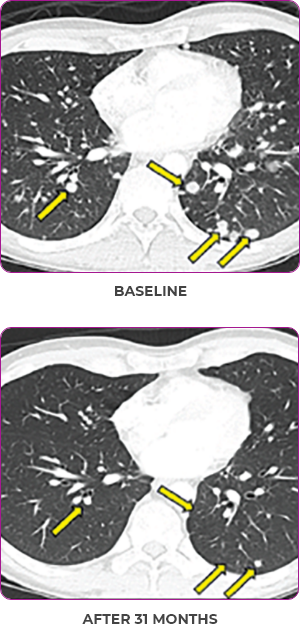

BASELINE

AFTER 31 MONTHS

PATIENT CASE:

METASTATIC, RAIa-REFRACTORY,

PAPILLARY THYROID CANCER1,2

- 33-year-old male

- Progression on RAI and first line systemic therapy

- PRa after 2 cycles of VITRAKVI® (larotrectinib)

- Confirmed partial response on VITRAKVI lasting 55 cycles

Response to VITRAKVI1,2

- Confirmed partial response (92.6% reduction in target lesions)

- Treatment continued for 55 cycles

- VITRAKVI was well tolerated; patient did not have to discontinue due to AEa

- No treatment interruptions or dose reductions

Response in primary and metastatic lesions1

Images courtesy of Dr Steven Waguespack.